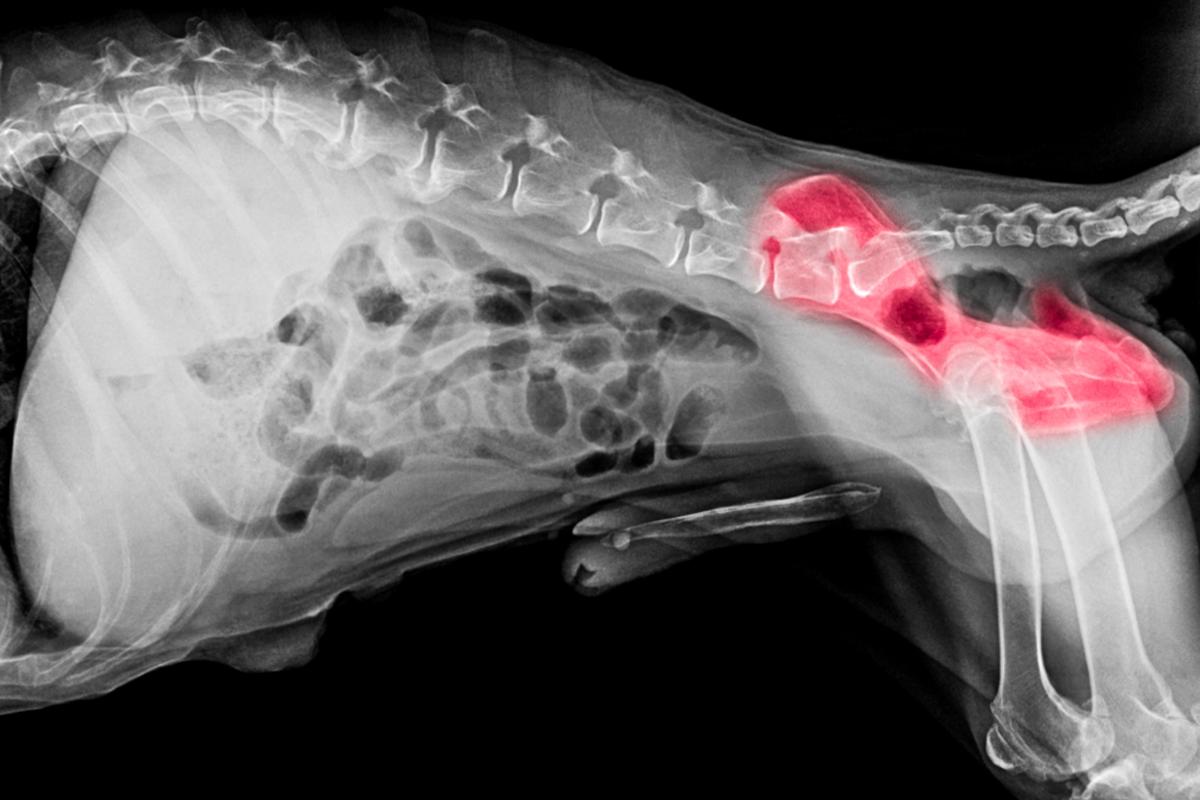

Para diagnosticar la osteoartritis canina, es clave realizar una buena anamnesis y exploración física del perro, junto con pruebas de diagnóstico por imagen. Veamos en qué consiste dichas pruebas:

- Diagnóstico por imagen: la prueba de elección suele ser la radiografía para detectar cambios como estofitosis y degeneración, pero su uso es limitado para obtener información de los tejidos blandos circundantes. Para obtener información de los tejidos blandos, se pueden utilizar otras técnicas como la resonancia magnética, mientras que para realizar un estudio más detallado de los cambios óseos se puede recurrir a la tomografía computarizada o TAC, especialmente indicada para las articulaciones de anatomía compleja como los codos, tarsos y carpos.